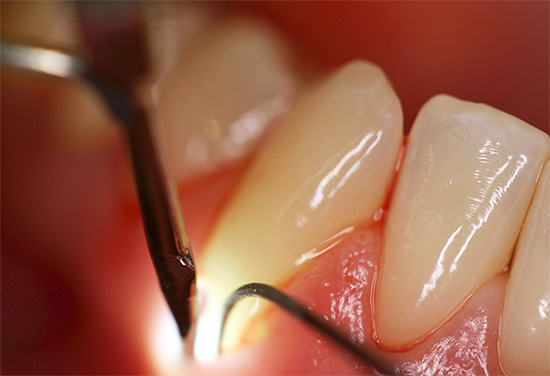

- Suono della superficie della radice. In questo caso, viene utilizzata solo una sonda appuntita, che consente di distinguere i tessuti sani dalle carie colpite dalla caratteristica rugosità superficiale.